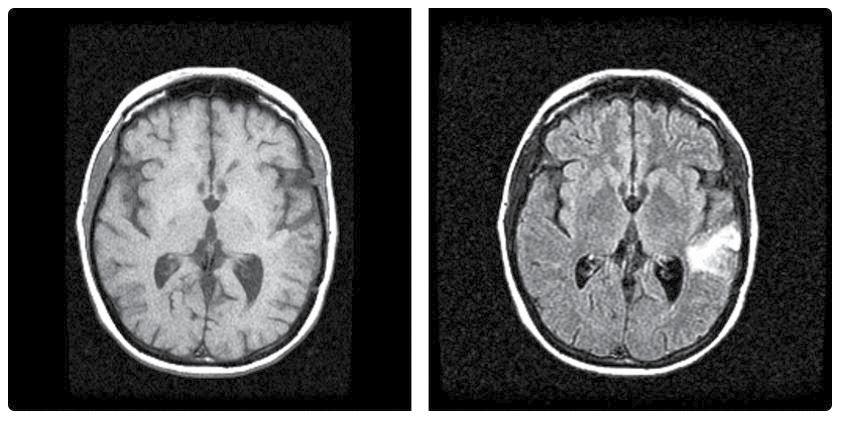

Apesar de los desafíos que plantea el alzhéimer, los avances recientes son motivo de optimismo. Las nuevas terapias, la investigación de una posible vacuna y su detección por los valores en sangre, están mostrando resultados prometedores, al tiempo que las tecnologías de diagnóstico están mejorando la capacidad de intervenir lo antes posible para ofrecer a los pacientes una mejor calidad de vida. Según la revista científica online JAMA Neurology, se ha documentado una mayor y más rápida precisión diagnóstica para la patología del alzhéimer. Un reciente estudio divulga que podría detectarse a través de una analítica de sangre.

Caracterizada por el deterioro cognitivo y la pérdida de memoria, esta enfermedad aparece cuando en las placas cerebrales se produce un exceso de la proteína beta-amiloide, esencial para la transmisión de información entre neuronas, y la disminución de otra, el tau positivo, empeorando el proceso cognitivo. Antes incluso de que aparezcan los primeros síntomas, estos depósitos van formando placas entre las neuronas que resultan tóxicas y son las responsables del progresivo deterioro cognitivo.

Terapias basadas en anticuerpos monoclonales

Uno de los avances más prometedores en el tratamiento ha sido el desarrollo de terapias basadas en anticuerpos monoclonales. Estos tratamientos incluyen medicamentos como lecanemab, de solución líquida intravenosa comercializado como Leqembi, cuyo uso médico está aprobado desde enero 2023 en EE. UU., pero en estado de revisión en Europa. Su mecanismo de acción es un anticuerpo monoclonal IgG1 humanizado que se une a las protofibrillas solubles de beta-amiloide, disminuyendo así la aglomeración de estas, las cuales empeoran el alzhéimer al formar placas seniles en la sustancia gris del cerebro y degenerar el sistema nervioso.

Este tipo de anticuerpo mostró resultados alentadores en ensayos clínicos al ralentizar significativamente el deterioro cognitivo en pacientes con alzhéimer leve. Los estudios indican que, al reducir la acumulación de placas de betaamiloide, lecanemab podría ofrecer una mejoría real en la calidad de vida de los pacientes, marcando

un avance crucial en el tratamiento de la enfermedad.

Diagnóstico temprano, factor fundamental

El diagnóstico temprano es crucial para tratar el alzhéimer de manera efectiva. Recientes avances en imágenes cerebrales y biomarcadores han mejorado la detección precoz de la enfermedad, permi -

tiendo intervenir en fases más tempranas.

El Centro de Investigación de Enfermedades Neurológicas (CIEN), de Madrid, cuenta con un nuevo escáner de resonancia magnética, el Magnetom Cima.X, que duplica la potencia de los anteriores modelos, ofreciendo una resolución que podría detectar cambios en el cerebro mucho antes de que aparezcan los primeros síntomas clínicos. Para ello, se experimenta con voluntarios mayores de 60 años, sin diagnóstico previo, que participan con un test digital, análisis de sangre y resonancia.